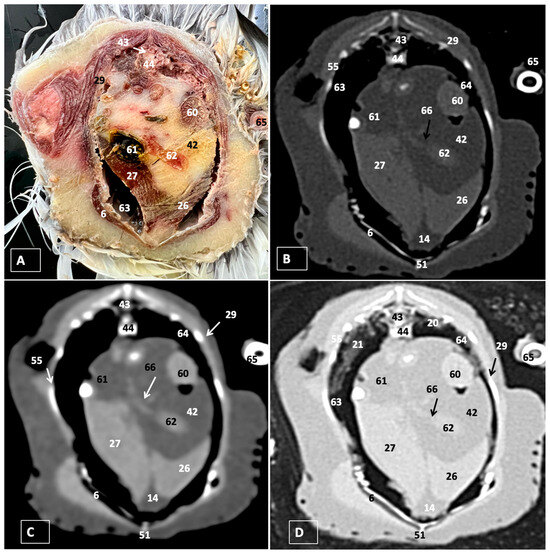

3. Results

3.1. Anatomical Dissections and Cross-Sections

3.2. Computed Tomography Images